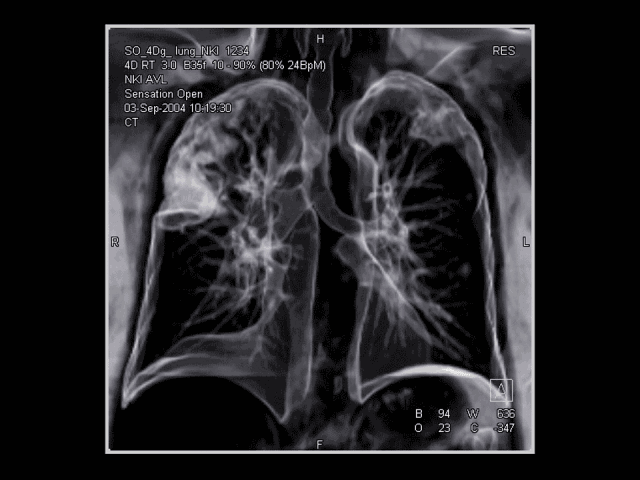

03胸腔器官动态CT显示